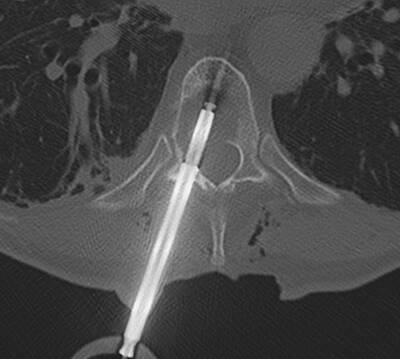

* Wirbelsäulenmetastasen: Bei Metastasen in der Wirbelsäule, die schwer zugänglich sind oder ein hohes Risiko für neurologische Schäden mit sich bringen, kann die IORT helfen, das Tumorgewebe gezielt zu behandeln und so im Einzellfall eine gute lokale Tumorkontrolle ohne anschliessende Nachbestrahlung zu ermöglichen. Diese Methode befindet sich in Augsburg in experimenteller Erprobung.

Die Intraoperative Radiotherapie (IORT) ist eine spezialisierte Behandlungsoption für Patienten mit Gehirntumoren und Wirbelsäulenmetastasen. Bei dieser Technik wird während einer Operation eine hochdosierte Strahlentherapie direkt an den Tumorbereich abgegeben, nachdem der Tumor chirurgisch entfernt wurde. Die IORT ermöglicht eine präzise Bestrahlung von Tumorgewebe, das möglicherweise nicht vollständig entfernt werden konnte, während gesundes Gewebe in der Umgebung geschont wird.

Insgesamt bietet die Intraoperative Radiotherapie eine vielversprechende Möglichkeit, Tumoren gezielt zu behandeln, insbesondere in schwierigen anatomischen Bereichen wie dem Gehirn und der Wirbelsäule. Sie stellt eine wertvolle Ergänzung zur klassischen chirurgischen Tumorentfernung und externen Strahlentherapie dar.